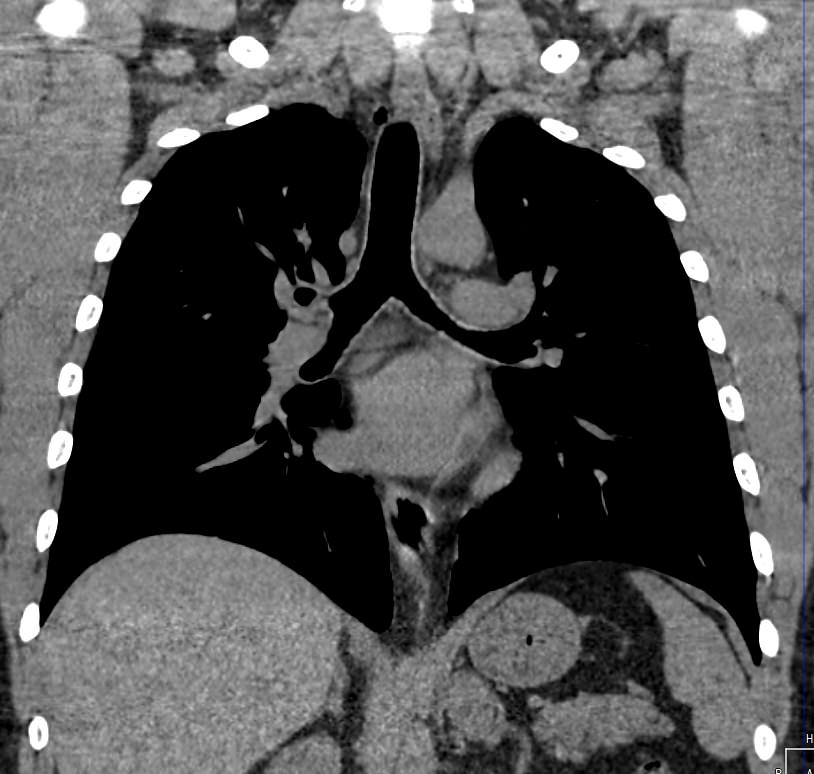

Средостение – анатомическое пространство в середине грудной клетки, которое с боков ограничено легкими, спереди грудиной, сзади позвоночником. В средостении располагаются органы, окруженные жировой клетчаткой, крупные кровеносные сосуды и нервы. К органам средостения относятся: пищевод, трахея, главные бронхи, вилочковая железа (тимус), сердце, аорта, верхняя и нижняя полые вены, нервы, лимфатические узлы.

Одним из наиболее информативных методов исследования органов средостения является компьютерная томография. В основе метода лежит использование проникающего действия ионизирующего излучения для получения подробных снимков строения внутренних органов.

Инновационные технологии, которыми оснащены компьютерные томографы, послойно сканируют анатомическую область с шагом от 0,5 мм. В результате получаются снимки тонких срезов исследуемой зоны в мельчайших подробностях. С помощью цифровых приложений на основании полученных данных можно реконструировать трехмерные модели внутренних органов, что позволяет оценить структуру зоны исследования и близлежащих тканей.

При сканировании на мультиспиральном компьютерном томографе можно выявить следующие патологии органов средостения:

- опухоли вилочковой железы (тимомы), липомы, лимфомы, липосаркомы и другие опухоли средостения, кисты тимуса, бронхогенные кисты;

- опухоли пищевода, грыжи пищеводного отверстия диафрагмы;

- загрудинный зоб;

- аневризмы аорты и ее плечеголовных ветвей;

- аномалии развития органов средостения;

- травматические повреждения органов грудной клетки, пневмоторакс, гемоторакс, обнаружение инородных тел средостения;

- патологии лимфатических узлов средостения при туберкулезе, саркоидозе, пневмокониозах, метастатическом поражении.